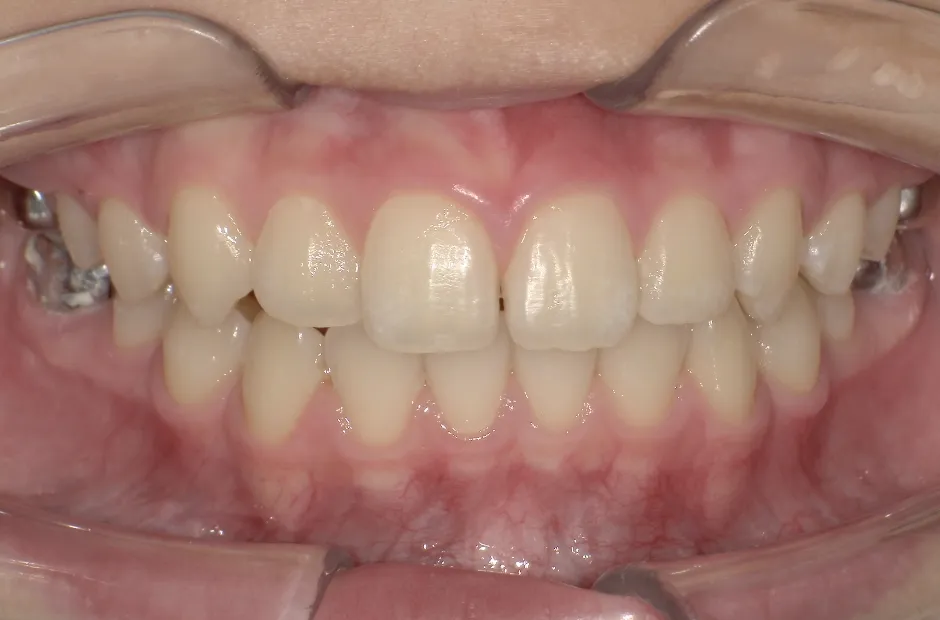

反対咬合

| 診断名・主訴 | 前歯反対咬合 |

|---|---|

| 年齢・性別 | 12歳・男性 |

| 治療期間・回数 | 1年半 18回 |

| 治療に用いた主な装置 | リンガルアーチ(前方誘導弾線) |

| 抜歯部位 | なし |

| 治療費 | 35万円(税抜) |

| リスク・副作用 | 装置による違和感・疼痛・歯肉退縮・歯根吸収・虫歯のリスクなど |